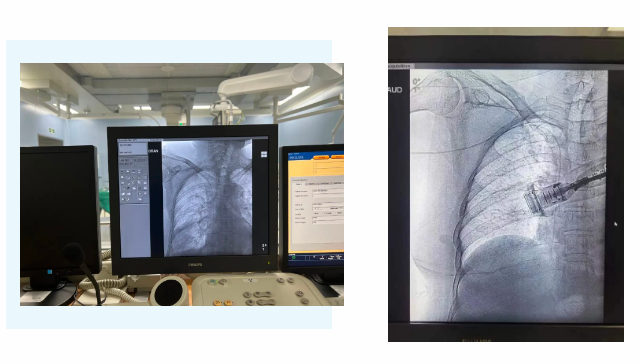

在麻醉手術(shù)中心的配合下,手術(shù)首先由韓海靜護(hù)士長(zhǎng)在超聲引導(dǎo)下應(yīng)用“塞丁格”法穿刺將針尖一樣細(xì)的導(dǎo)絲送入血管,術(shù)中在DSA透視下將導(dǎo)管沿著血管送達(dá)上腔靜脈,尖端精準(zhǔn)定位至上腔靜脈開(kāi)口處。隨后,胸腔外科支亞男主治醫(yī)師在穿刺點(diǎn)下方取2厘米小切口內(nèi)進(jìn)行上臂港囊袋和隧道的制作及導(dǎo)管與港座連接,最后進(jìn)行港體埋植及皮內(nèi)縫合,使患者切口隱蔽美觀(guān)創(chuàng)傷小,術(shù)中出血量極少。手術(shù)在X片影像留影,最終手術(shù)順利完成。